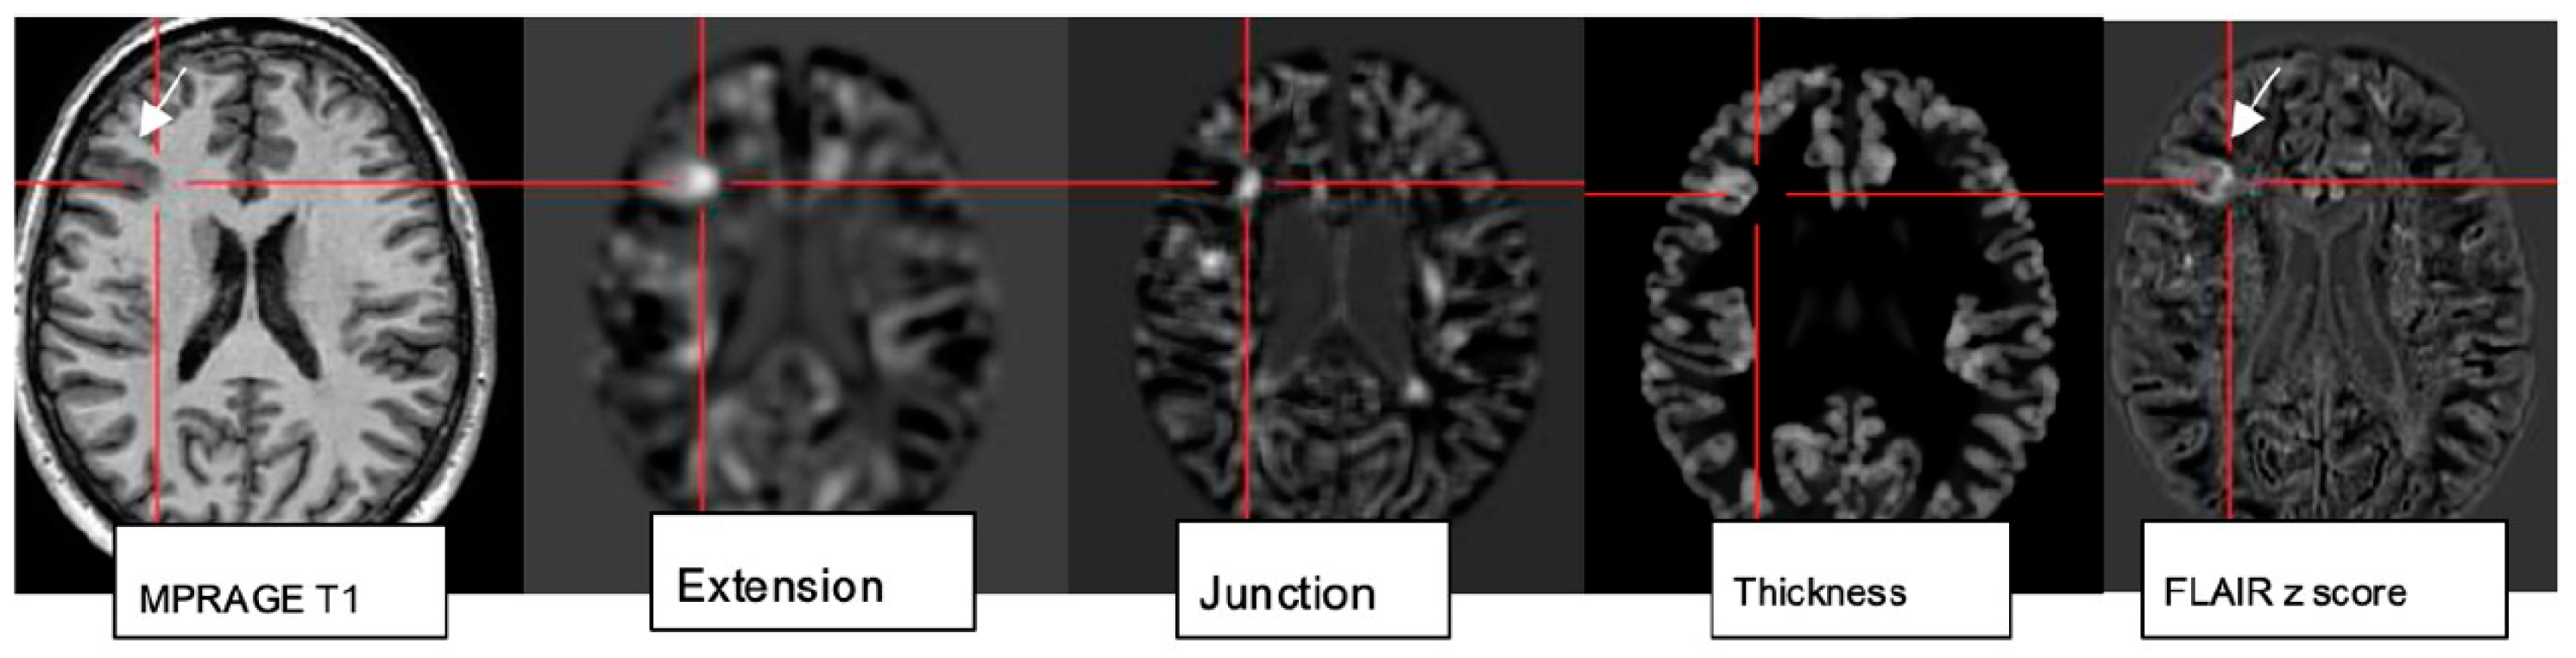

4.6. Postprocessing by Morphometric Analysis Improves Focal Lesion Detection Beyond Visual Analysis

While visual analysis alone based on higher signal and spatial resolution increases the conspicuity of small pathologies, combination with postprocessing techniques (normalization, segmentation, and subtraction/division from a database of normal controls) and submission to a morphometric analysis program proved particularly beneficial to identify lesions that are beyond immediate visual recognition [78]. The morphometric maps created within the morphometry analysis program (Figure 6) encompass the MRI hallmarks of focal cortical dysplasia: abnormal extension of gray into white matter and configuration of deepened sulci, abnormal thickening of the cortical ribbon, and blurring of the gray–white matter junction. These are used to create morphometric extension, thickness, and junction maps. The “combined map” represents the maximum z score of the three maps for each voxel but is still finally verified by visual analysis [79].

Morphometric analysis by normalization, segmentation, and subtraction/division from a database of healthy controls results in the calculation of z score maps: extension corresponds to abnormal gyration/sulcation, location of gray matter (GM); junction signifies blurring of GM-WM border; and “thickness” depicting cortical thickening in a patient with right frontal FCDIIb (see MPRAGE T1, FLAIR z score image).

Rapid analysis of a 3D MP2RAGE dataset in conjunction with a side-by-side comparison of FLAIR sequences increases sensitivity and reduces false-positive findings by morphometry. The generation of probability maps for lesions such as FCD in the future will further benefit from the integration of artificial neuronal networks [80].